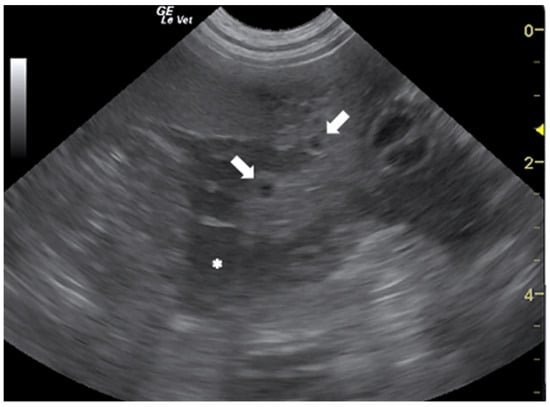

- Corda, A.; Dessì, G.; Varcasia, A.; Carta, S.; Tamponi, C.; Sedda, G.; Scala, M.; Marchi, B.; Salis, F.; Scala, A.; et al. Acute visceral cysticercosis caused by Taenia hydatigena in lambs: Ultrasonographic findings. Parasites Vectors 2020, 13, 568. [Google Scholar] [CrossRef]